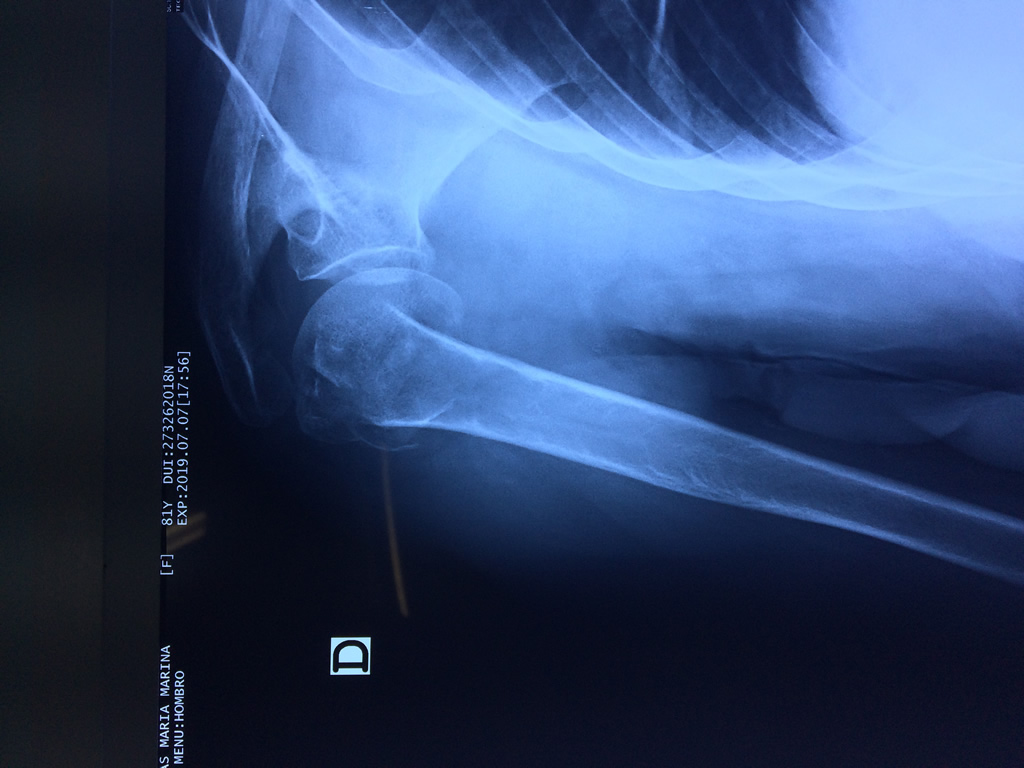

Varias estructuras transparentes en forma de saco llamadas bolsas serosas, permiten el deslizamiento suave de los diferentes componentes móviles. El hombro es la articulación con mayor amplitud de movimientos del cuerpo humano.